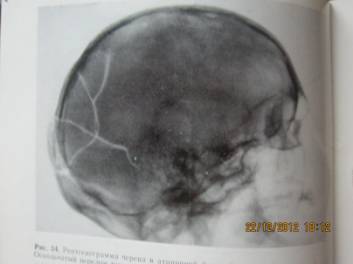

задней черепной ямки. Во всех 4-х группах. Это объясняется тем, что при ударно - волновом и механическом

воздействии вследствие передачи костям

черепа кинетической энергии формируется гидродинамический удар, действующий на

структуры голоного мозга и внутреннего уха (прямо и опосредовано). (cм Рисунок 1-4)

Рисунок 1